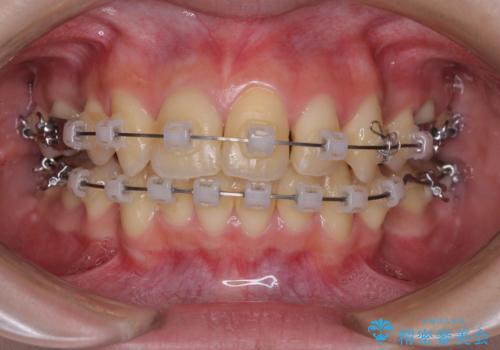

- クリアブラケット

- 1年10ヶ月

- 上下の出っ歯を気にして来院された患者様です。

口元を積極的に引っ込めるために、上下左右の小臼歯を4本抜歯することとしました。

右上前から2番目の歯が欠損しているため、①矯正治療により欠損部にスペースを作りインプラント補綴を行って前歯を左右対称に揃える、②左右非対称となるが、欠損補綴を行わずに排列する、のいずれかとなりますが、患者様と相談の上②にて矯正治療を行うこととしました。

変則的な歯列であったため、奥歯がしっかりと咬み合うのか、前歯はしっかりと排列できるのかと不安ではありましたが、結果としてはきれいに整った歯列にて終了することができました。